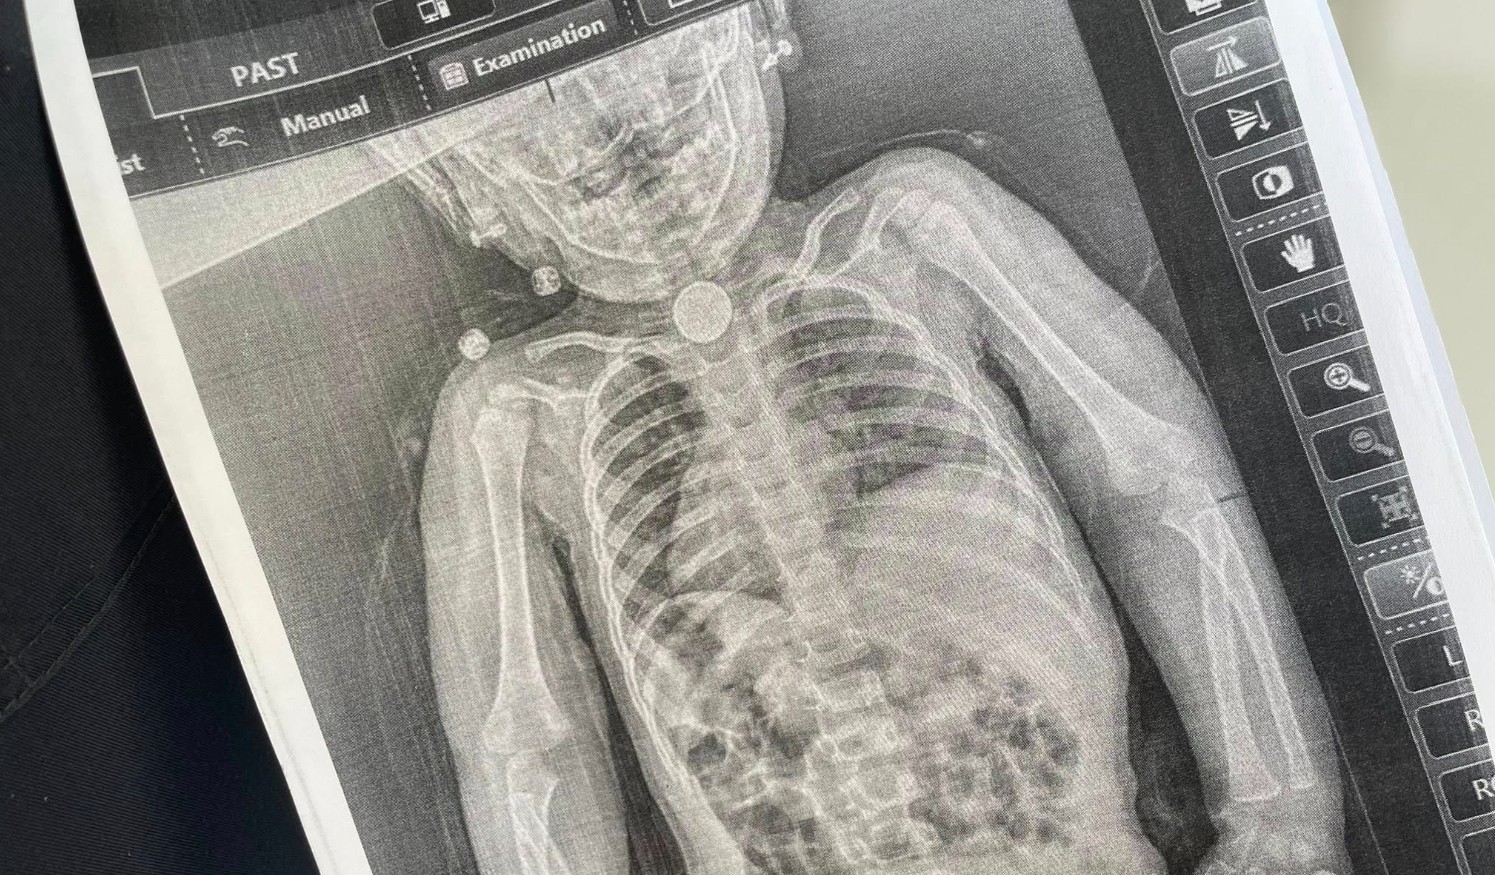

У перші дні весни у дитини з’явилися нові небезпечні симптоми: блювання, відмова від їжі, покашлювання та свистяче дихання, яке було чути навіть на відстані. Батьки знову повезли дочку до лікарні та наполягли на додатковому обстеженні. Дівчинці зробили рентген, який чітко показав стороннє тіло у стравоході.

Вже під час ендоскопічного обстеження точно встановили, що ж це було. У ділянці першого фізіологічного звуження стравоходу міцно застрягла кругла літієва батарейка діаметром 2,5 см. Навколо неї сформувалися набряк та гіпергрануляції слизової оболонки — ознаки тривалого ушкодження тканин.